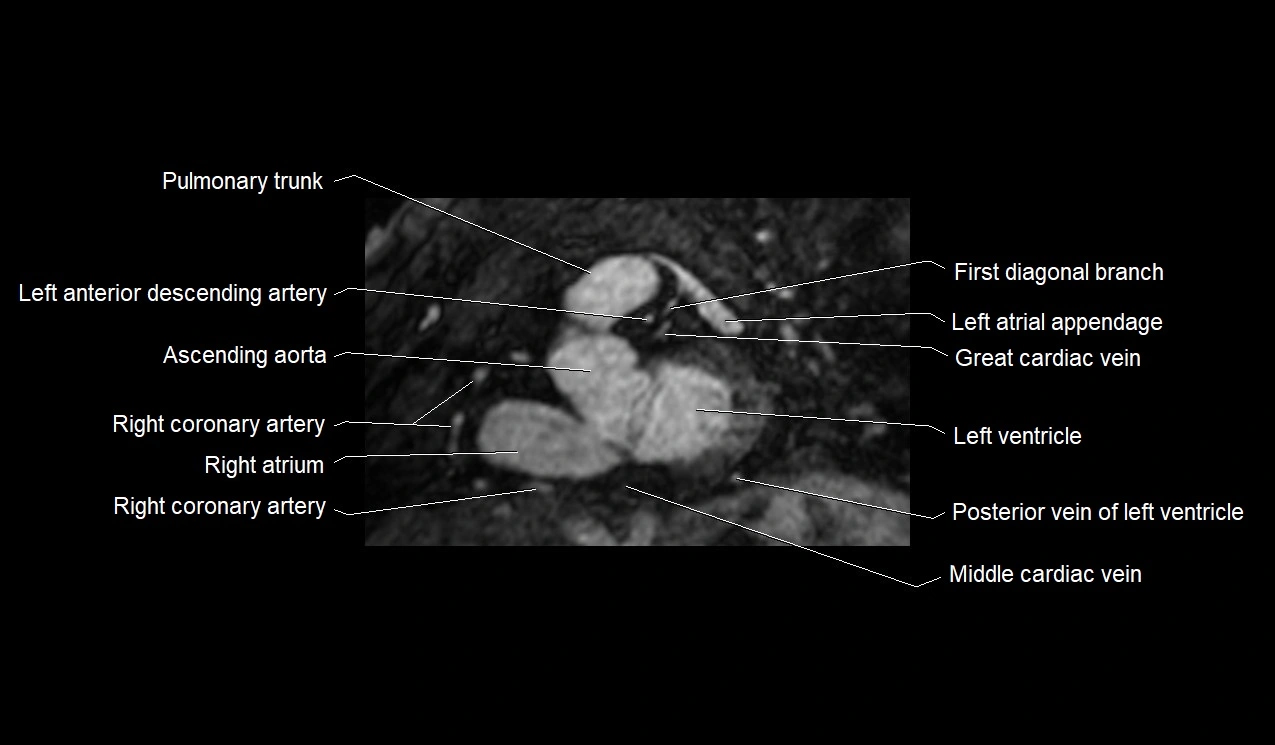

- Pulmonary trunk

- Left anterior descending artery (LAD)

- Ascending aorta

- Right coronary artery (RCA)

- Great cardiac vein

- First diagonal branch (D1) of LAD

- Left ventricle

- Right atrium

- Posterior vein of left ventricle

- Middle cardiac vein